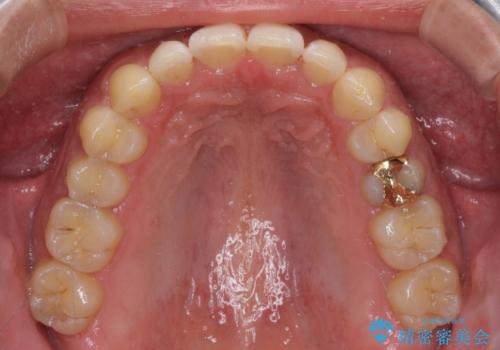

- 上顎前歯の突出感とすきっ歯を気にして来院された患者様です。

奥歯の咬み合わせを見ると、下顎に対して上顎が前方に位置していたため、補助装置により上顎歯列全体を後方に移動させ、その後インビザラインにて歯列全体を整えることとしました。